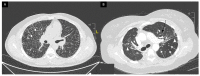

Sarcoidosis is a multi-system disease of unknown etiology characterized by the formation of granulomas in various organs. It affects people of all ethnic backgrounds and occurs at any time of life but is more frequent in African Americans and Scandinavians and in adults between 30 and 50 years of age. Sarcoidosis can affect any organ with a frequency varying according to ethnicity, sex and age. Intrathoracic involvement occurs in 90% of patients with symmetrical bilateral hilar adenopathy and/or diffuse lung micronodules, mainly along the lymphatic structures which are the most affected system. Among extrapulmonary manifestations, skin lesions, uveitis, liver or splenic involvement, peripheral and abdominal lymphadenopathy and peripheral arthritis are the most frequent with a prevalence of 25-50%. Finally, cardiac and neurological manifestations which can be the initial manifestation of sarcoidosis, as can be bilateral parotitis, nasosinusal or laryngeal signs, hypercalcemia and renal dysfunction, affect less than 10% of patients. The diagnosis is not standardized but is based on three major criteria: a compatible clinical and/or radiological presentation, the histological evidence of non-necrotizing granulomatous inflammation in one or more tissues and the exclusion of alternative causes of granulomatous disease. Certain clinical features are considered to be highly specific of the disease (e.g., Löfgren's syndrome, lupus pernio, Heerfordt's syndrome) and do not require histological confirmation. New diagnostic guidelines were recently published. Specific clinical criteria have been developed for the diagnosis of cardiac, neurological and ocular sarcoidosis. This article focuses on the clinical presentation and the common differentials that need to be considered when appropriate.